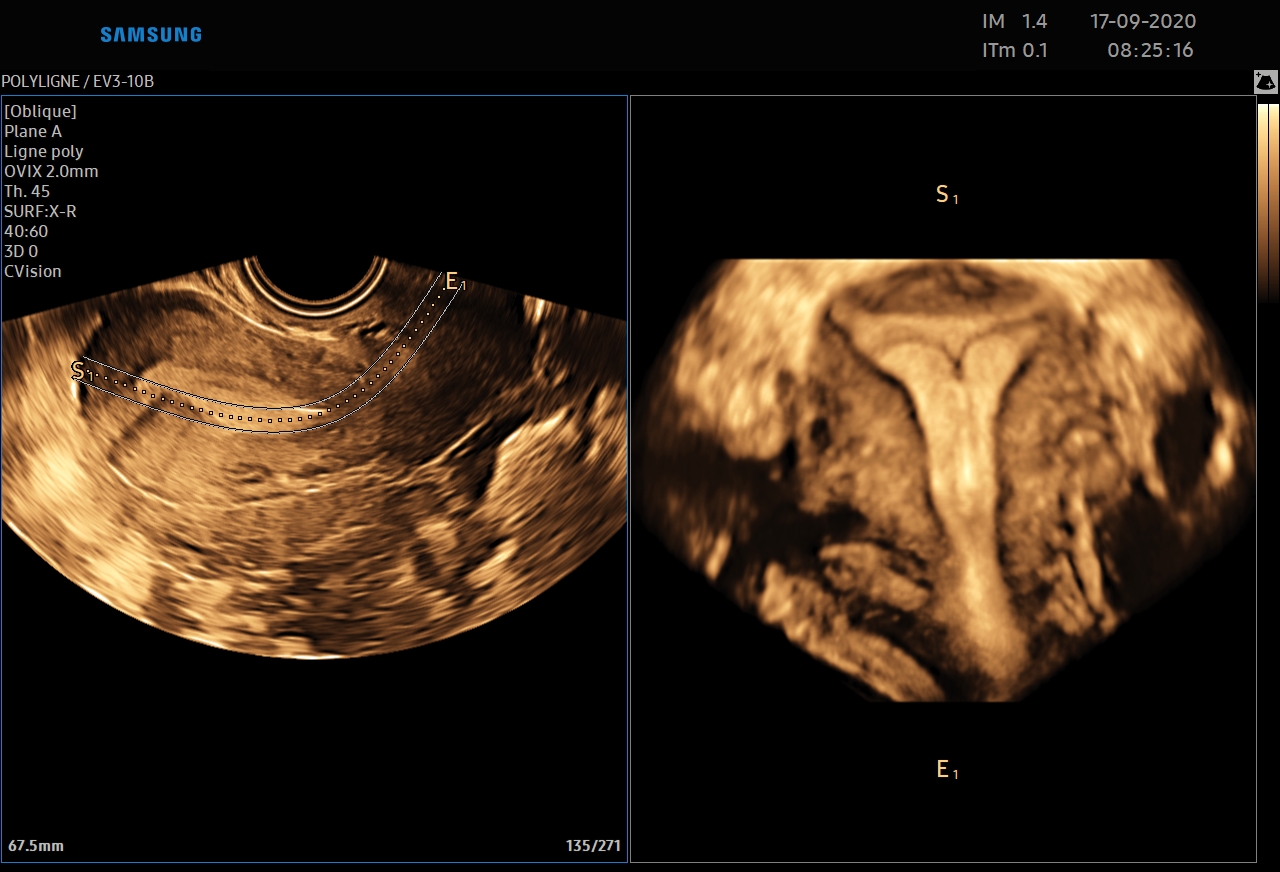

Le 5D CNS+™ est un module qui permet de générer et de reconstruire 9 plans de coupe automatiquement à partir d'une acquisition volumique sur le cerveau fœtal. Les calipers sont positionnés automatiquement par l'échographe à la demande de l'utilisateur.